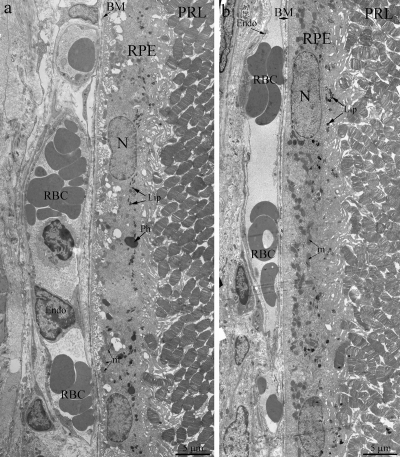

Light- and electron microscopy did not relive significant differences in structure of retina of OXYS and Wistar rats at 20 days and 3 months. The RPE layer has one line of cells with normal localized nucleus, endoplasmic reticulum, ribosome and mitochondria (Figure 2). On the Figure 2 endothelial cells, which formed the wall of choriocapillaries, cavity of choriocapillaries and erythrocyte in it are good visible. But already at the age of 20 days, along with normally functioning choriocapillaries, we observed appearance choriocapillaries with stasis of blood cells. (Quantity analysis of choroid vessels and RPE cells see below).

Figure 2. Outer retina of Wistar (a) and OXYS (b) rats at the age of 3 months. PRL – photoreceptors, RPE – retinal pigment epithelial cell, N – RPE nucleus, m – mitochondrion, Ph – phagosome, Lip – lipofuscin material, BM – Bruch's membrane, Endo – endothelial cell, RBC – red blood cell.